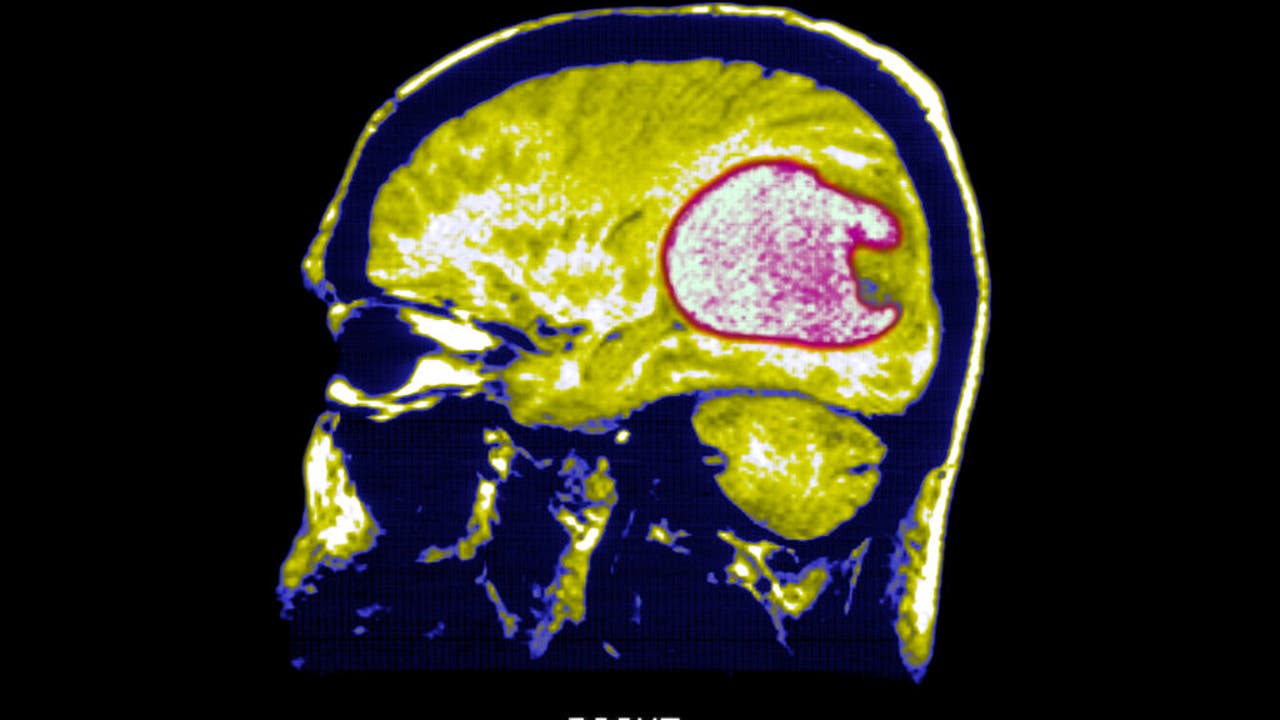

WASHINGTON - A fresh approach to battling an aggressive form of brain tumor has shown promise in small-scale experiments involving a few patients.

Scientists transformed immune cells from the patients into "living drugs" capable of identifying and attacking glioblastoma, a type of brain cancer. Initial tests revealed that these cells managed to shrink tumors, albeit temporarily, as researchers reported on Wednesday.

Glioblastoma, the type of brain cancer that claimed the lives of Beau Biden, son of President Joe Biden and longtime Arizona Senator John McCain, is notoriously fast-growing and challenging to treat. Patients typically survive for 12 to 18 months following diagnosis, and despite years of research, there are limited options for treatment once the cancer recurs after surgery and radiation.

Mass General conducted tests on three patients using CAR-TEAM, and brain scans revealed rapid tumor shrinkage shortly after, according to the researchers' report in the New England Journal of Medicine.